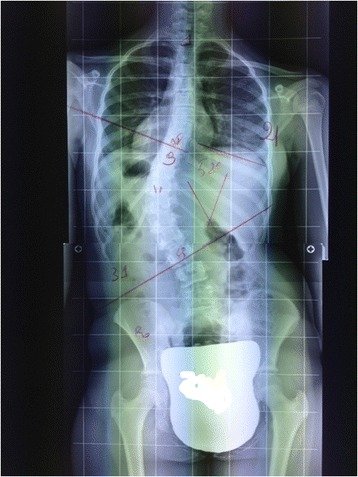

Scoliosis is a spinal deformity that affects around 2-3% of the population. It involves a side to side (lateral) and twisting (rotational) deviation from the spines normal alignment. The vast majority of scoliosis is idiopathic, meaning there is no specific cause, and usually develops during teenage years.

In the Chiropractic setting, we focus primarily on treatment of mild-moderate scoliotic curves, and ideally we start management early on in their progression. We also treat severe cases, but typically only if they have had a surgical consult first and are deemed non-surgical or have very low risk of progressing. Our treatment goals include symptom relief, improving spinal flexibility and posture, and reducing the scoliosis curve angle as well as risk of angle progression. Treatment is a combination of hands-on therapy techniques for quicker short-term relief, and scoliosis “curve correction” exercises that have been shown to reduce the scoliosis curvature and reduce risk of scoliosis curve progression in mild-moderate cases. Read below to understand how we assess a spine with scoliosis and what treatment options we can provide.

In the clinic we take rotational curve measurements to track and monitor for scoliosis curve progression.

This type of curve measurement is different than an x-ray measurement, but like an x-ray measurement it helps us to monitor for changes in the curve angle as someone ages and grows.

For teens with a mild scoliosis and/or lower risk of progression x-rays are not usually recommended by most family doctors, so physical exam curve measurements are the main curve tracking method.